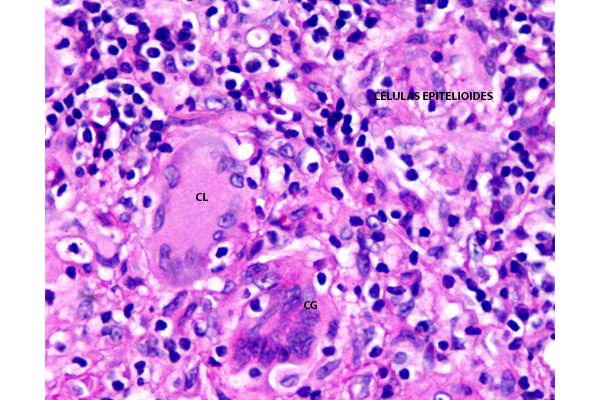

Este infiltrado es típicamente granulomatoso e incluye, macrófagos, células gigantes multinucleadas de tipo Langhans y de tipo cuerpo extraño, formadas por la fusión de macrófagos, así como linfocitos y células plasmáticas, especialmente en la periferia de los granulomas.

Destaca la presencia de células gigantes multinucleadas de tipo Langhans y de tipo cuerpo extraño.

Abundantes células gigantes de tipo Langhans (CL), de tipo cuerpo extraño (CG) y células epitelioides, en el espesor de los granulomas.